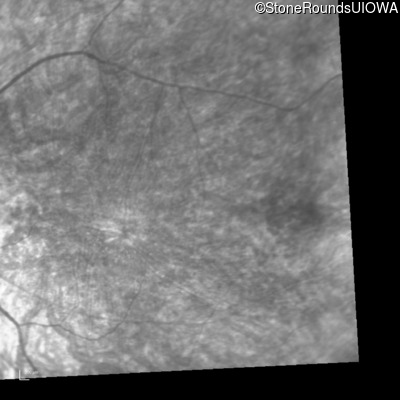

Infrared Fundus Photograph - Right - 20/200 +2

Exemplar